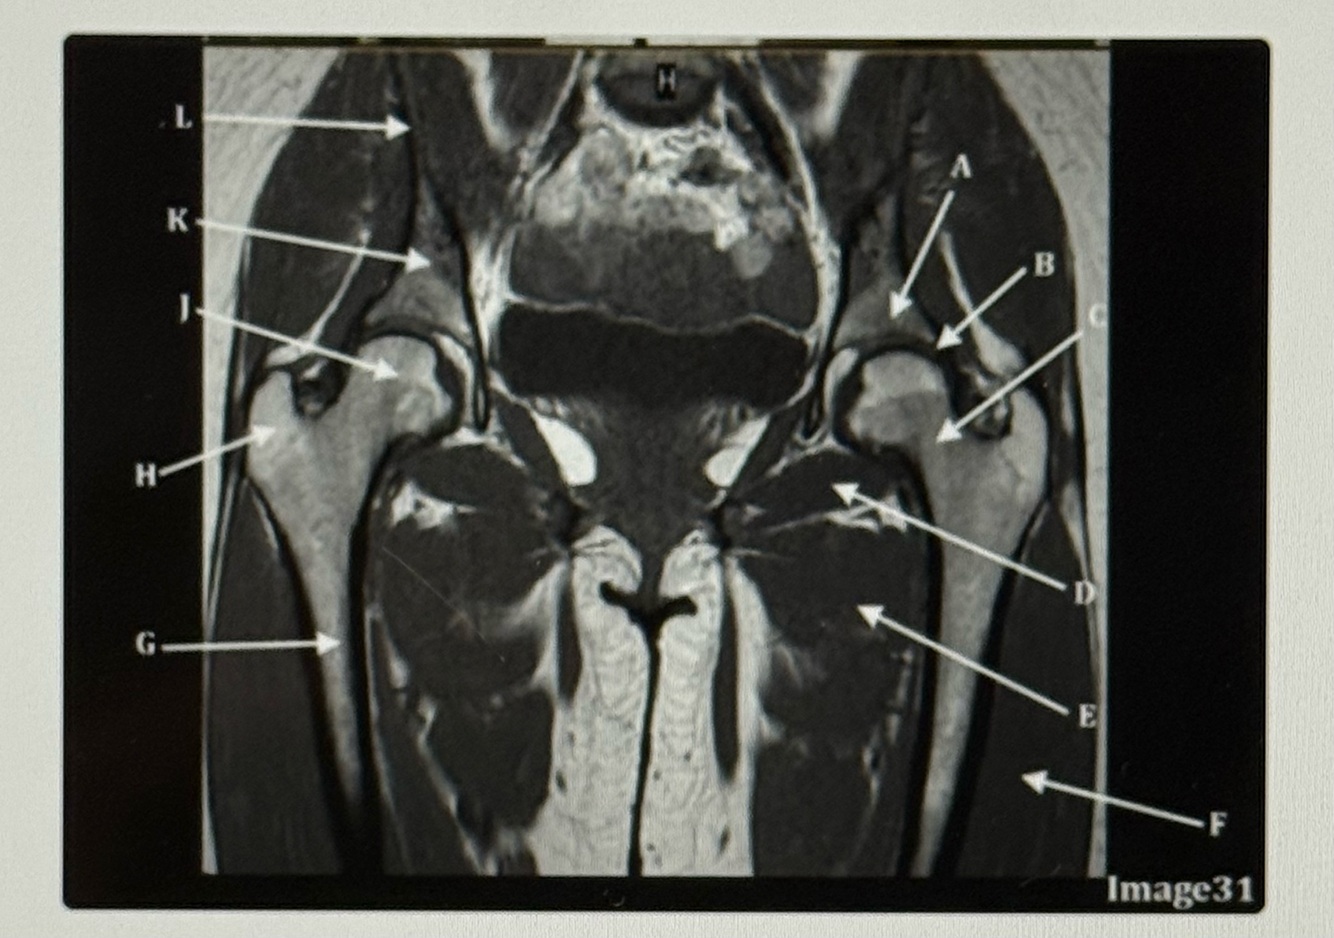

Letter A points to the

A

Acetabulum

Q

Letter B points to the

Labrum

Letter C points to the

Femoral neck

10

Letter D points to the

Obturator externus

11

Letter E points to the

Adductor muscles

12

Letter F points to the

Vastus lateralis

13

Letter G points to the

Femur

14

Letter H is pointing to the

Greater trochanter

15

Letter J points to the

Femoral head

16

Letter K points to the

Body of the ilium

17

Letter L points to the